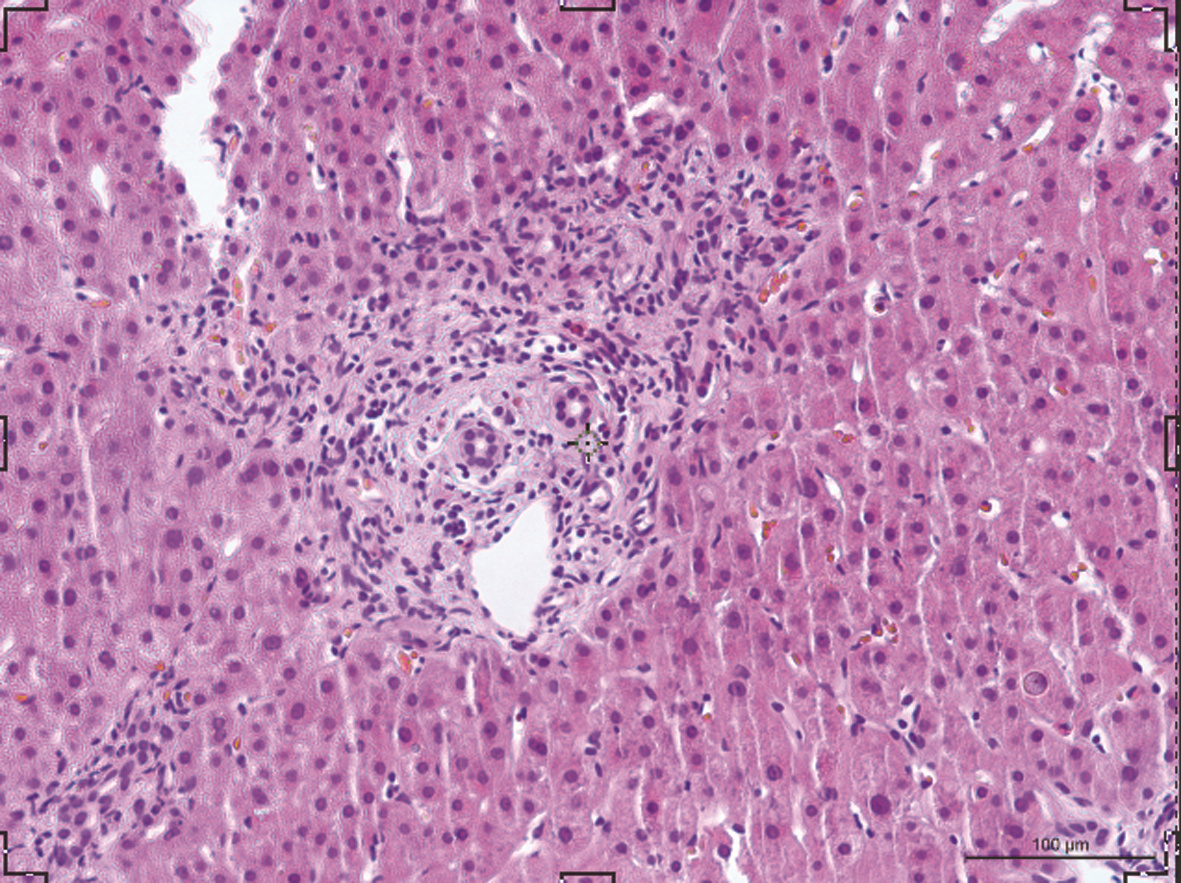

Objective  To investigate the expression level of neutrophil extracellular traps (NET) in the peripheral blood and liver tissue of primary biliary cholangitis (PBC) patients and its correlation with clinical biochemical parameters.  Methods  A total of 24 PBC patients who were admitted to Renji Hospital, Shanghai Jiao Tong University School of Medicine, from August 2016 to August 2020 were enrolled, as well as 8 patients with primary sclerosing cholangitis (PSC) and 19 patients with autoimmune hepatitis (AIH) matched for age, and 19 healthy individuals were enrolled as healthy control group (HC group). The serum level of myeloperoxidase (MPO) was measured, and its correlation with clinical indices were analyzed. Immunofluorescence assay was used to measure the expression of NET in the liver of PBC patients, and an in vitro experiment was to compare the ability of peripheral blood neutrophils to produce NET between PBC patients and healthy controls. Normally distributed continuous data were expressed as mean±standard deviation, and the independent samples t-test was used for comparison between two groups; for the non-normally distributed continuous data expressed as M(P25-P75), the Kruskal-Wallis H test was used for comparison between multiple groups, and the Mann-Whitney U test was used for comparison between two groups. A correlation analysis was performed for MPO level and liver-related laboratory markers, and the Spearman's correlation coefficient was calculated.  Results  The serum level of MPO in the PBC group was increased to 811.21 (450.67-1 216.20) ng/mL, which was significantly higher than that in the AIH group [468.58 (142.63-812.43) ng/mL] and the HC group [357.54 (203.52-811.21) ng/mL] (P < 0.05), suggesting that there was a significant increase in the production of NET in peripheral blood of PBC patients. The PSC patients had a serum MPO level of 763.56 (489.59-1 633.14) ng/mL, which was significantly higher than that in the HC group (P < 0.05). MPO level was positively correlated with alkaline phosphatase (r=0.500, P < 0.05), gamma-glutamyl transpeptidase (r=0.426, P < 0.05), alanine aminotransferase (r=0.521, P < 0.05), and aspartate aminotransferase (r=0.547, P < 0.01). Confocal immunofluorescence showed colocalization of H3Cit and MPO in the liver of PBC patients. In vitro experiment showed that compared with the HC group, the PBC group had an increase in NET produced by peripheral blood neutrophils after in vitro stimulation and an increase in spontaneous production of NET.  Conclusion  There is an increase in NET in peripheral blood and liver of PBC patients, and the content of peripheral blood NET is positively correlated with biochemical parameters of liver function. NET may become a novel biomarker for assessing the severity of PBC.

Autoimmune hepatitis (AIH) is an immune-mediated liver disease with hepatocytes as the main target cells. It is characterized by the high immunoglobulin G level and the presence of autoantibodies, and histological observation shows interface hepatitis at the portal area caused by a large amount of lymphoplasmacytic infiltration. The pathogenesis of AIH has not been fully elucidated. At present, glucocorticoid combined with azathioprine is mainly used as non-specific immunosuppressive therapy, and most patients tend to have good response; however, rebound or relapse is often observed during dose reduction or after drug withdrawal, so most patients need long-term maintenance therapy. This article briefly reviews the advances in the pathogenesis of AIH and the potential new targets for clinical intervention, in order to provide a reference for clinical translational research.